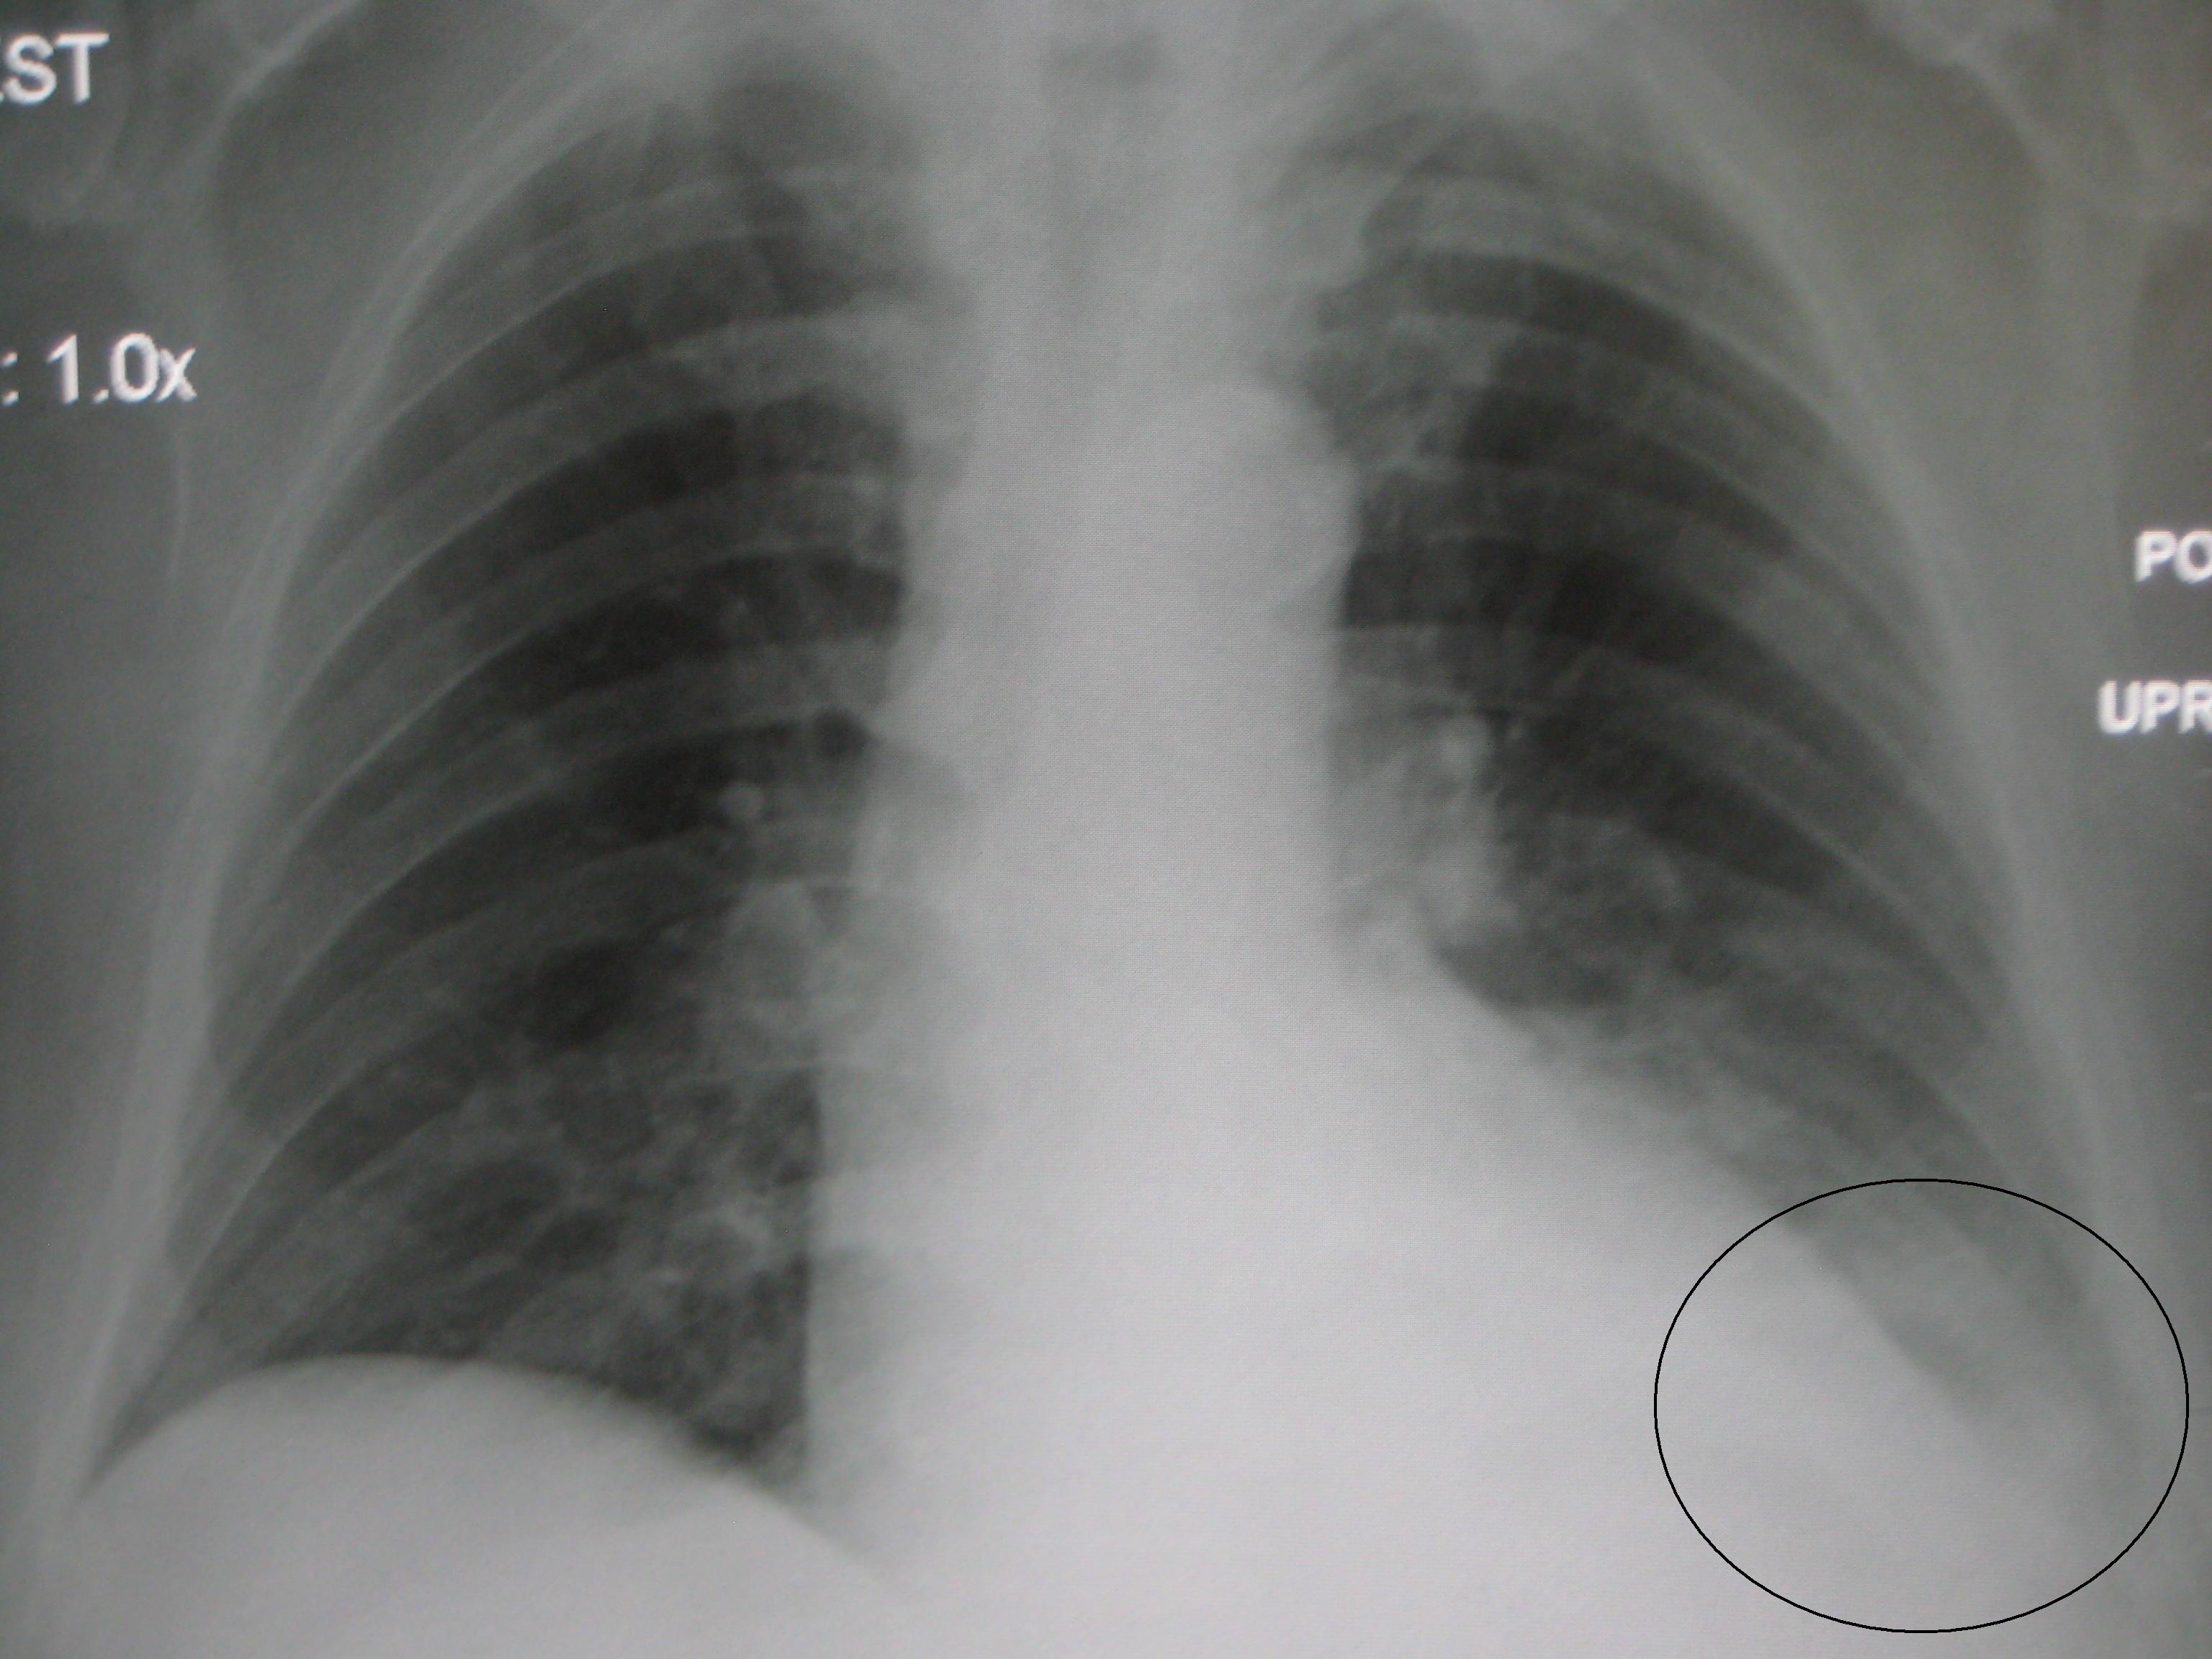

기립 X선에서 75 mL의 체액이 뒤쪽 갈비가로막오목을 둔화시킨다. 측면 갈비가로막오목의 둔화는 일반적으로 약 175 mL가 필요하지만 최대 500 mL가 소요될 수 있다. 더 큰 가슴막 삼출은 반쪽 가슴의 일부를 불투명하게 만들고 가슴세로칸 변위를 유발할 수 있다. 삼출액이 4 L를 초과하면 반쪽 가슴의 완전한 불투명화와 반대쪽으로의 가슴세로칸 변위를 유발할 수 있다.[2]

가슴막 삼출로 인해 발생한 액체는 똑바로 선 자세에서 갈비가로막오목으로 모이며,[4] 단순 X선 촬영에서 갈비가로막각이 커지는(둔각에 가까워지는) 결과로 나타난다.[2] 가슴 X선은 가슴막 삼출의 존재를 확인하기 위해 실시하는 첫 번째 검사이다. 가슴막 삼출이 의심되는 경우 똑바로 서서 가쪽 가슴 X선을 촬영해야 한다. 뒤쪽 갈비가로막각이 가장 먼저 커지며, 액체가 많아질수록 가쪽의 갈비가로막각도 커지게 된다. 가슴막 삼출로 인한 액체가 더 많아지면 가슴 절반을 완전히 불투명하게 만들고, 가슴세로칸을 반대로 이동시킬 수 있다.

가슴막 삼출로 인해 발생한 액체는 똑바로 선 자세에서 갈비가로막오목으로 모이며,[4] 단순 X선 촬영에서 갈비가로막각이 커지는(둔각에 가까워지는) 결과로 나타난다. 가슴 X선은 가슴막 삼출의 존재를 확인하기 위해 실시하는 첫 번째 검사이다. 가슴막 삼출이 의심되는 경우 똑바로 서 가쪽 가슴 X선을 촬영해야 한다. 뒤쪽 갈비가로막각이 가장 먼저 커지며, 액체가 많아질수록 가쪽의 갈비가로막각도 커지게 된다. 가슴막 삼출로 인한 액체가 더 많아지면 가슴 절반을 완전히 불투명하게 만들고, 가슴세로칸을 반대로 이동시킬 수 있다.[2]